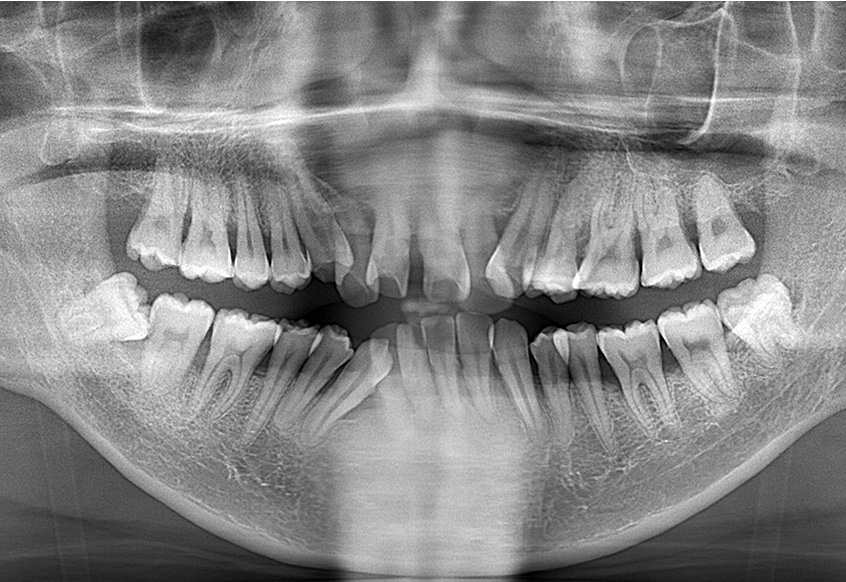

2024.6.25パノラマレントゲン写真

-

親知らずの痛みがなくなった患者さんは、昔から歯並びが気になっていることを打ち明けてくれました。特に上の歯が少し前に出ていたり、隙間があったりしている点を治したいそうです。そこで、まず上の歯並びの矯正治療を開始しました。